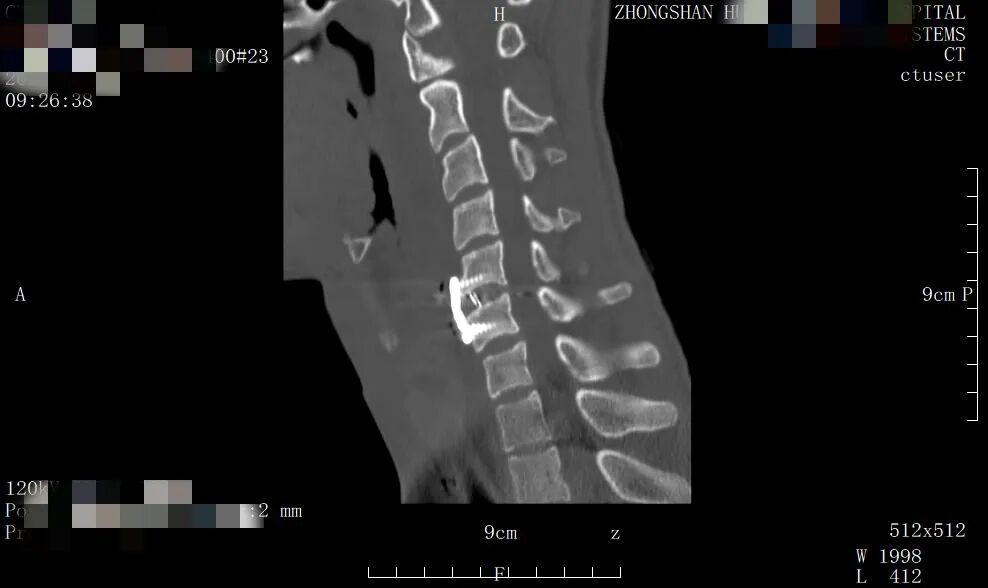

▲术后X光片

术后,在科室护理团队的精心照护和早期康复指导下,患者在支具保护下可下床活动。术前存在的四肢麻木、无力症状得到显著缓解,肌力逐渐恢复,生活质量得到了根本性的提升。目前患者已康复出院。